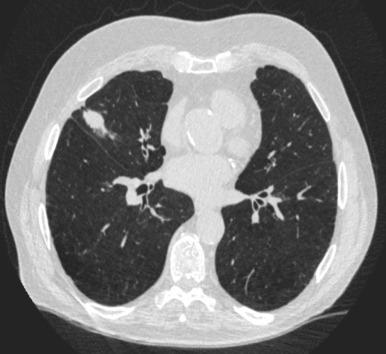

At present, no agent or combination of agents has been proven to delay or prevent the development of lung cancer in high-risk populations. The emphasis in this population has been early detection, previously with chest radiographs and now most notably with low-dose screening chest CT ( Fig. 51.1 ). NSCLC is a disease well suited for a comprehensive screening program for a number of reasons. The disease is common and represents a significant health problem, especially in a high-risk population that has a clearly identifiable risk factor of tobacco exposure. Lung cancer is often asymptomatic until the disease is advanced, at which point it has a high mortality rate even with treatment. Effective therapies are available for early-stage lung cancer. As tumor size and stage are highly prognostic, it is most advantageous to diagnose the disease as early as possible. A sensitive screening test is essential to an effective screening program that preferably has limited morbidity, is accessible to the at-risk population, and is economical relative to the consequences of an unscreened population.

Fig. 51.1, Computed tomography scan of a 78-year-old man with a screen detected cT1c N0 non–small cell lung cancer.